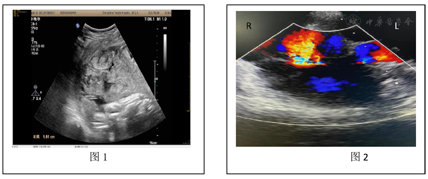

(1)2021年9月20日急诊B超:宫内单胎妊娠;宫内异常回声团块,考虑血块可能,胎盘显示不清,以上征象未排胎盘早剥可能。未及胎心。BPD:93 mm,HC:323 mm,AC:285 mm,FL:66 mm。宫腔内见一高回声为主团块,范围约136 mm×49 mm(图1)。(2)术中床旁经食管心脏超声提示右心室增大,肺动脉高压声像(图2)。

诊断依据:两次剖宫产史,围分娩期出现典型的无法用其他原因解释的突发心脏骤停,凝血功能障碍,术中食管心脏超声见肺动脉高压声像图,典型的腹痛、阴道流血、无间歇的宫缩、板状腹、未闻及胎心,B超见宫内异常回声考虑血块可能,未见胎儿心跳,凝血功能检查提示APTT、凝血酶原时间延长,纤维蛋白原极低,3P阳性,D二聚体异常升高,产后24 h估计总出血量4 100 ml。紧急行剖宫取胎术,住院期间最低血红蛋白78 g/L,入院血压稍高,术后血压超过160/110 mmHg,产后一直需要降压药控制约10 d,伴器官功能损害。